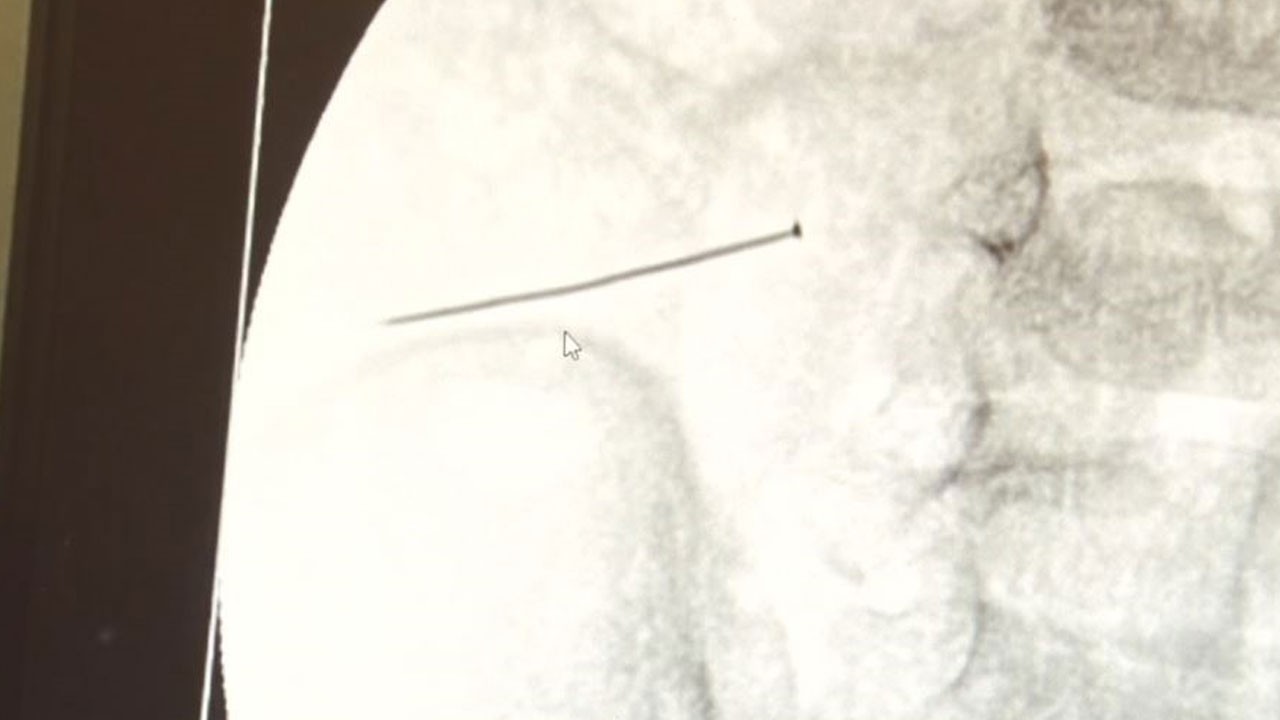

Öte yandan, yaklaşık 3 santimlik toplu iğne filme yansıyan görüntüsüyle gözler önüne serildi.

Babaanne, küçük çocuğun şikayetleri üzerine Şehit Prof. Dr. İlhan Varank Sancaktepe Eğitim ve Araştırma Hastanesi’ne götürdü. Burada yapılan tetkiklerde 2 yaşındaki çocuğun ince bağırsağında yaklaşık 3 santimlik toplu iğne olduğu ve bağırsağı deldiği belirlendi. Görüntülemeler sonrası 30 Ekim akşamı Çocuk Cerrahisi Kliniği Eğitim ve İdari Sorumlusu Doç. Dr. Sefa Sağ ve ekibi hemen ameliyata girdi. Başarılı operasyonla iğne olduğu noktadan alınırken aile de rahat bir nefes aldı. Doç. Dr. Sağ ise taburcu edilen hastasının durumuna ilişkin bilgi verirken yabancı cisim yutmalarına karşı ailelere önemli uyarılarda bulundu.

Çocuklarda yabancı cisim yutulmasına yönelik konuşan ve hastasına ilişkin bilgi veren Doç. Dr. Sefa Sağ, "Soluk borusuna kaçması durumunda çocuğun Allah göstermesin ölümüyle veya ömür boyunca yatağa bağımlı kalmasıyla neticelenebilecek sonuçlar doğurabiliyor. Yutulması durumunda da gastrointestinal sistemin herhangi bir yerine takılmadığı müddetçe ekseriyâ yabancı cisimlerin dışarıya çıkmasını bekliyoruz. Yabancı cisim yutulmasını 2 grupta inceleyebiliriz. Sıvı ve katı cisimler olarak sıvı; evde kullanılan kimyasal temizlik malzemelerinin yutulması çok ciddi problemler oluşturabilmekte. Ağızda, yemek borusunda ve midede yanıklar meydana getirebilmekte. Uzun dönemde çocukların hayat kalitesini oldukça etkileyen sonuçlar doğurabilmekte. Katı cisimlerden de ekseriyâ kendiliğinden çıkmasını bekleriz ancak böyle delici, kesici aletlerin yutulmasında ise herhangi bir bağırsağın veya gastrointestinal sistemin bir parçasında delinmeler meydana getirebiliyor. Bu çocuğumuzda da aynen böyle bir hadise meydana gelmişti. Sanırım 1 gün önce ailenin yuttuğunu tahmin ettiği bir yabancı cisim; toplu iğne. Ertesi gün bağırsakta delinmeyle sonuçlanmış ve çocukta da ciddi semptomlar meydana getirmişti. Bu şekilde hasta bize başvurdu. Tetkikler sonucunda yabancı cismi tespit ettik, semptomları ve bulgularına göre de çocuğu ameliyata aldık. Yaklaşık 3 santim boyunda bir toplu iğnenin ince bağırsağı deldiğini, ince bağırsaktaki içeriğin de karın içerisine dolduğunu gördük. Ameliyatı başarılı bir şekilde tamamladık, yaklaşık 1 saat süren bir ameliyattı" dedi.